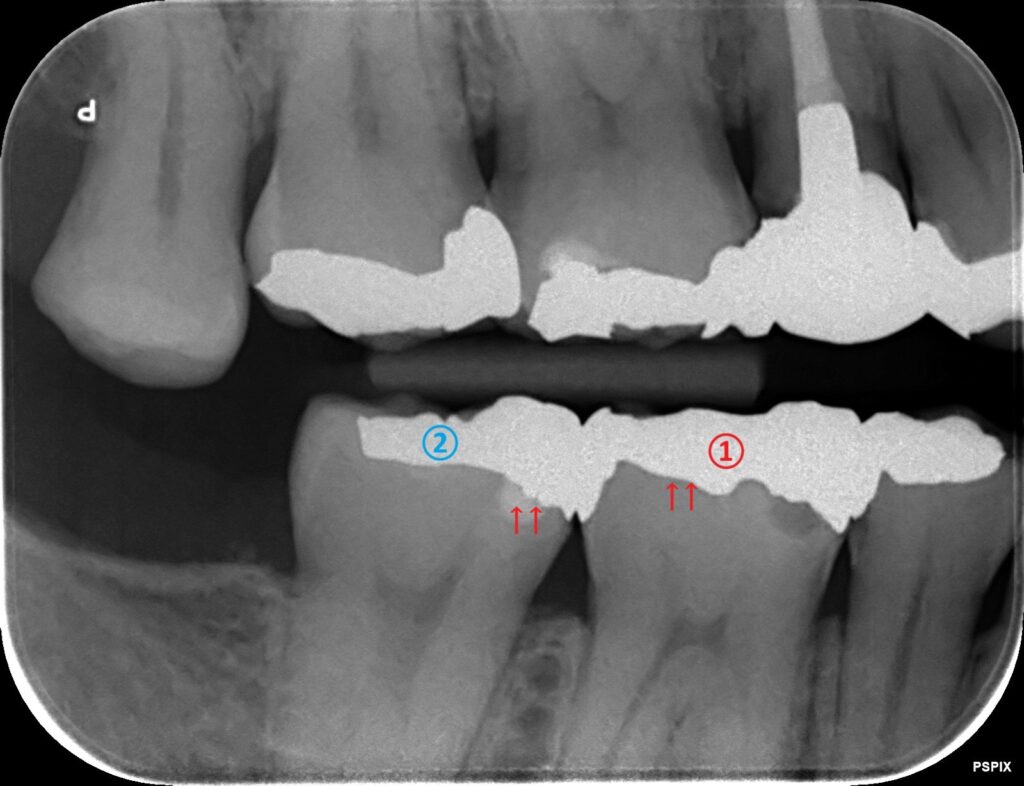

ナンバリングしてあります、①番と、②番の歯を見てみましょう。

①銀歯の中で分かった虫歯

レントゲン写真を確認してみると、

銀歯の下に黒く、丸い影が出ているのが分かりますでしょうか?

この記事の最初の方で説明したように、銀歯の下でも虫歯が大きければ虫歯の影を確認できます。

②銀歯を外してみて分かった虫歯

先ほどの続きで、②番の歯を見てみましょう。

同じように銀歯が入っている歯ですが、①番のように黒い虫歯の影が認められません。

銀歯はレントゲン写真で真っ白に写ってしまいます。

その銀歯直下で虫歯が広がっている場合は、虫歯が写らないので分かりません。

矢印の箇所の虫歯です。

つまり銀歯の下の虫歯は、大きく広がって進行している場合は確認できるが、銀歯の直下で小さく広がっている場合は確認できないと言えます。